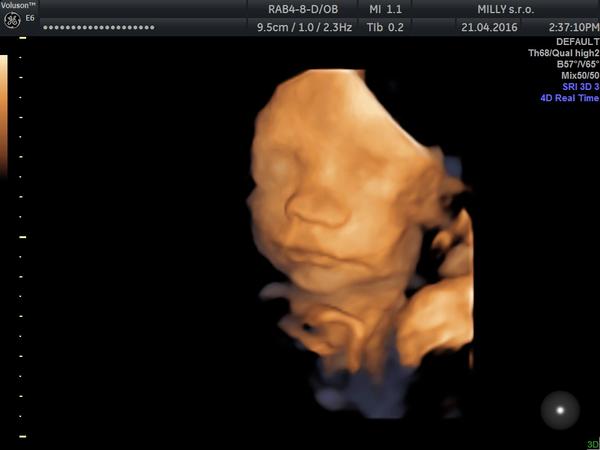

Ahojte žienky 🙂 Ideme sa zas raz pochváliť a čím ďalej tým viac so nesmierne vďačná, že existuje možnosť nám takto pomôcť aby sme mali to naše vytúžené zlatíčko u seba 🙂 Náš vysnívaný synček v 25tt 673g a jediná fotka, ktorú máme pretože sa nám nechcel za celých 30minút ukázať 🙂 Toľkú radosť prežívam a ďakujem, že môžem patriť medzi budúce mamičky 🙂 Nikdy sa nevdývajte a verte vo svoje sny, aby sa Vám naplnili 🙂